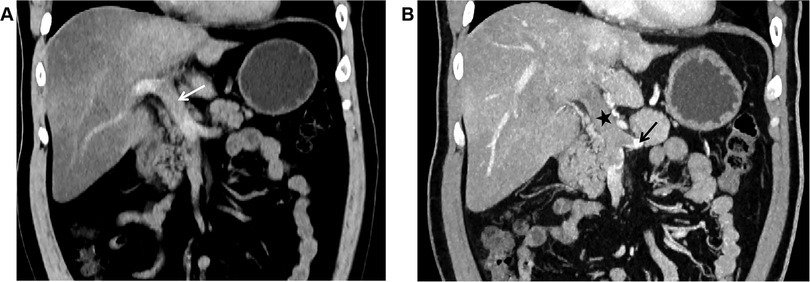

Unenhanced CT scan demonstrated dilation of the main portal vein trunk (diameter ∼1.89 cm) with heterogeneously increased intraluminal density (average CT value ∼45 HU, reaching up to 80 HU near the bifurcation), involving the left and right portal vein branches and the superior mesenteric vein (SMV) (Figure 1A). Portal venous phase clupontrast-enhanced CT revealed non-enhancing filling defects indicating complete occlusion of the main portal vein trunk, its left and right branches, the SMV, and the splenic vein (diameter ∼1.11 cm) (Figure 1B). Numerous tortuous, dilated collateral vessels with enhancement were noted periportally. The left gastric vein was dilated, draining into the left medial liver lobe; esophageal-gastric varices were not significantly dilated. Hypodensity was observed in the right lobe and lateral segment of the left lobe (CT value ∼30 HU), with significantly reduced enhancement compared to normal parenchyma. Bowel loops were normal in caliber without wall thickening, mesenteric stranding, obstruction, or abnormal enhancement. No ascites was present.

Figure 1. (A) In case 1, the non-contrast CT scan in the coronal plane of the abdomen shows widening of the main portal vein trunk (arrow), with unevenly increased density within the lumen, blurred margins of the vessel wall, and indistinct surrounding fat planes. (B) In Case 1, The CT scan with contrast during the portal venous phase in the coronal plane reveals filling defect changes in the main portal vein trunk (black star), along with the left branch and right branch, indicating complete occlusion of the lumen. The splenic vein (black arrow) is also involved, and no enhancement changes are noted in the filling defect area. The liver parenchyma exhibits reduced density, with significantly weakened enhancement post-contrast.